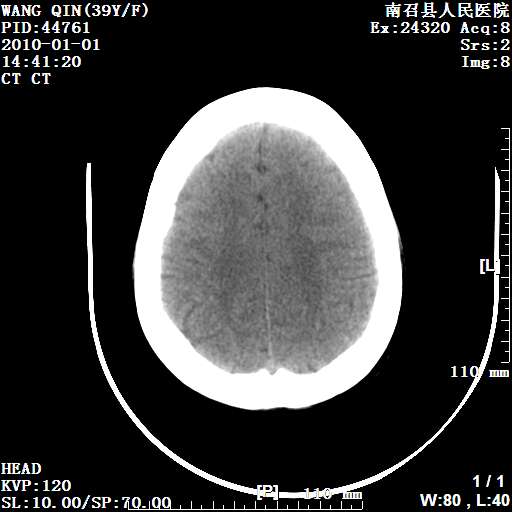

以下是引用随光逐影在2010-1-22 9:03:00的发言:[br]考虑左侧中颅窝(蝶骨翼区)脑膜瘤侵犯蝶骨翼并突入左侧眼眶。

以下是引用水过无痕在2010-1-22 14:55:00的发言:[br]一、定位:颅外占位;二、定性:恶性可能性大;三、组织来源:来源于左侧眼外直肌或其他部位;考虑为:横纹肌肉瘤>转移瘤>脑膜瘤.